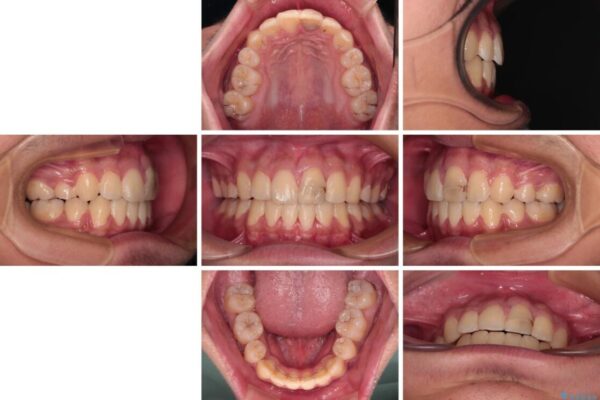

治療前

• 膨らんだ口元 ワイヤー装置での抜歯矯正 治療前画像